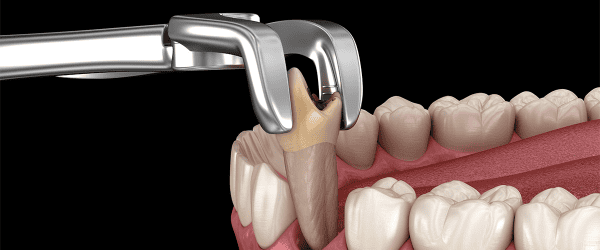

Our oral surgeon gently removes the wisdom teeth using precise techniques, minimizing trauma to surrounding tissue for a smooth recovery.

There are two main types: simple extractions for teeth visible above the gum line, and surgical extractions, such as wisdom tooth removal, for teeth that cannot be easily accessed.

We take measures to ensure the extraction process is as painless as possible, using local anesthesia to numb the area. Some discomfort following the procedure is normal but can be managed with prescribed pain relief.